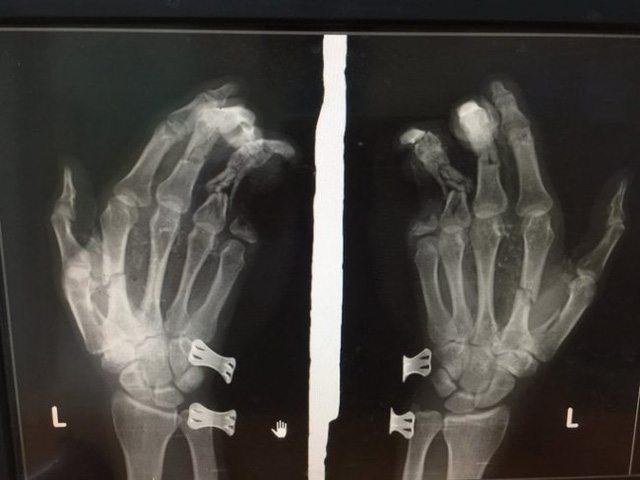

Thật khó có thể tin được nhưng chỉ trong vòng vài ngày ngắn ngủi của những ngày cuối năm 2021 và đầu năm 2022, đã xảy ra 2 vụ tai nạn thương tâm liên quan đến việc sử dụng điện thoại. Đầu tiên là bé trai ở Hà Tĩnh, vào khoảng 15h ngày 29/12, Trung tâm Y tế huyện Nghi Xuân - Hà Tĩnh đã tiếp nhận một bệnh nhân (sinh năm 2007) trong tình trạng dập nát bàn tay trái do nổ điện thoại. Các tổn thương ở bàn tay của bệnh nhân rất nặng. (Theo VOV).

Ảnh: VOV

Được biết, bệnh nhân vừa chơi điện thoại vừa sạc pin dẫn đến chiếc điện thoại phát nổ dẫn đến tai nạn thương tâm kể trên.

Cách đây không lâu, cháu K, 9 tuổi tại Hà Giang cũng bị điện thoại phát nổ làm dập nát bàn tay trái cùng với nhiều vết thương ở vùng ngực. Nguyên nhân cũng vì vừa cắm sạc điện thoại để chơi game. Vì vậy, người dùng điện thoại nên tuyệt đối tránh thói quen sử dụng nguy hiểm này để không phải nhận những hậu quả nghiêm trọng cho bản thân và gia đình.